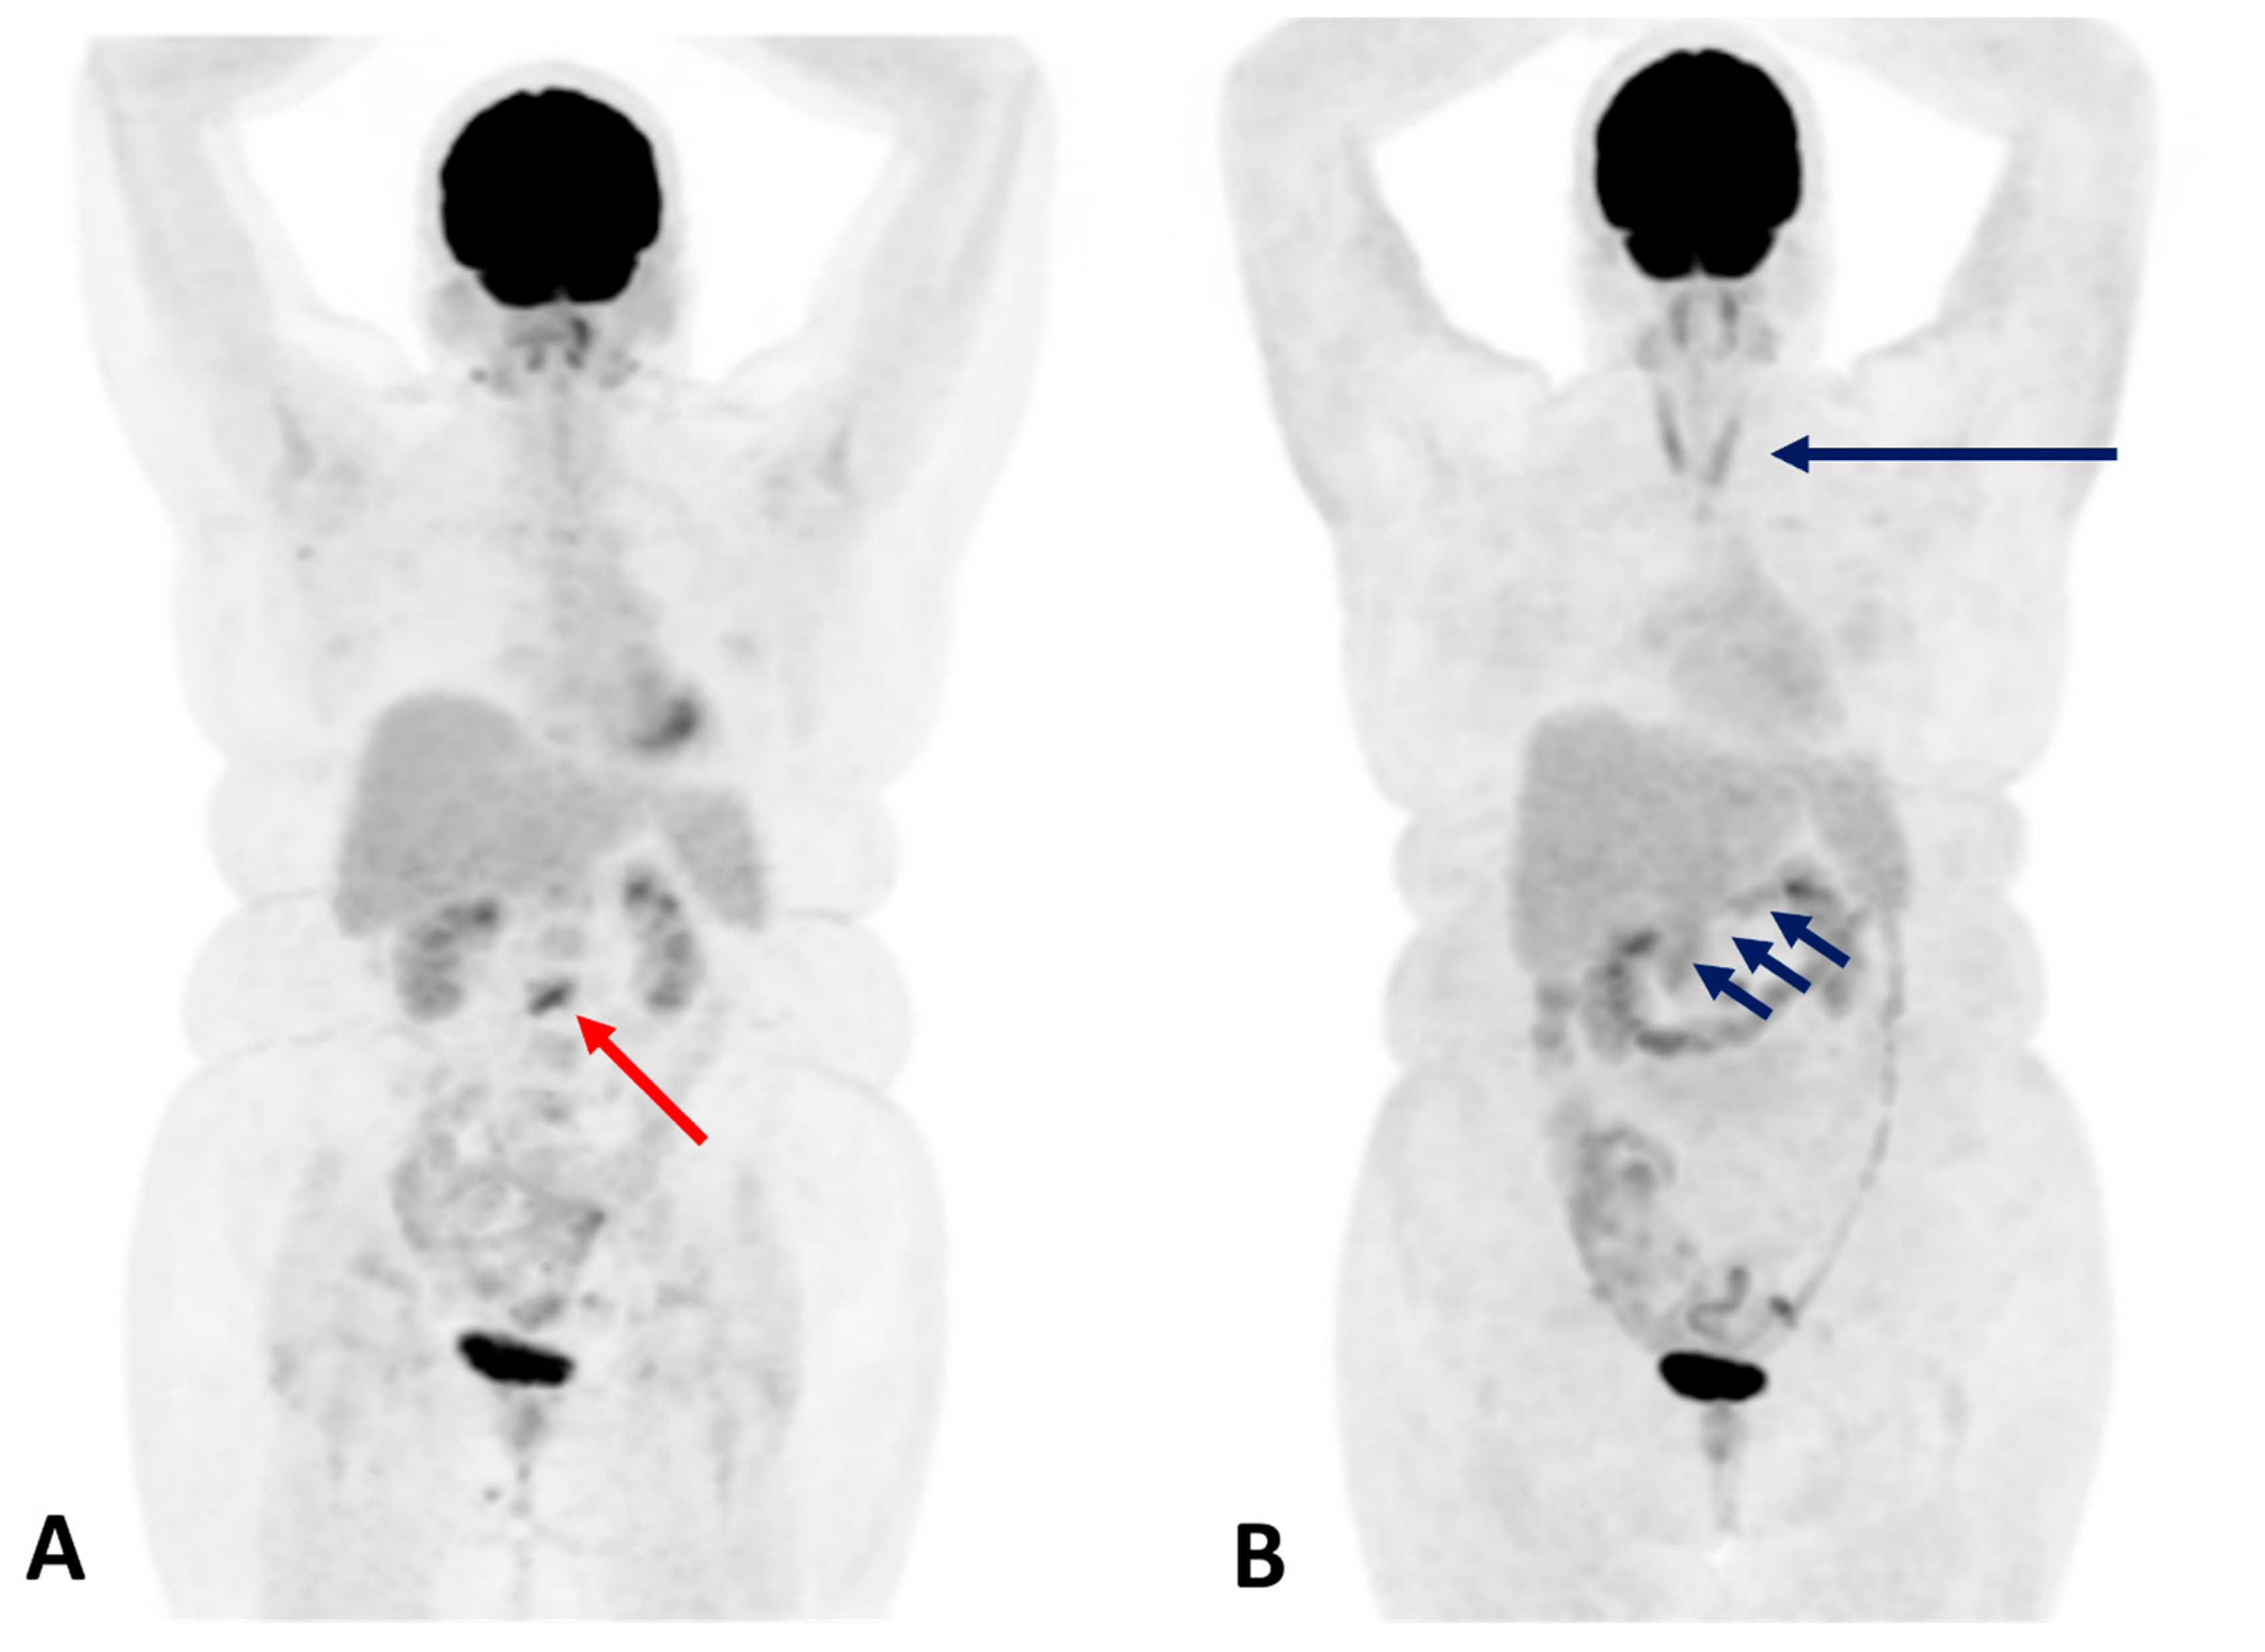

Figure 2. Immune-related thyroiditis in a 67-year-old male patient with colorectal cancer receiving Pembrolizumab at a dose of 2 mg/kg IV every 3 weeks for metastatic disease noted in the liver. PET maximum intensity projection (MIP) (A) and axial PET/CT fusion images (B) showed a diffuse increase in 18F-FDG uptake within the thyroid gland (red arrow) and 18F-FDG active liver metastasis (dark blue arrow).